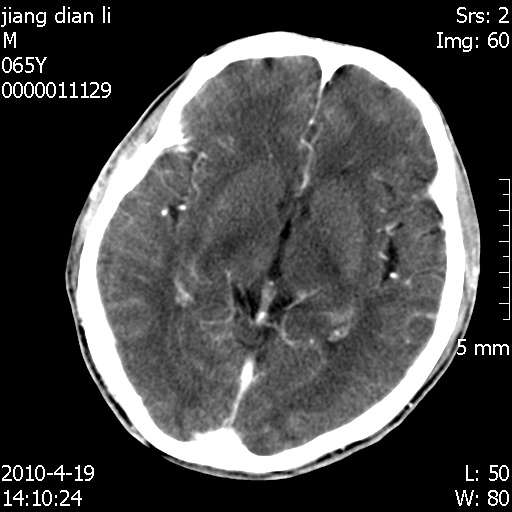

老年男性,突发左下肢无力1天,其余有价值的检查都没有。平扫ct值大约60hu,增强后ct值没什么改变,请大家讨论一下这个病例是什么?说明诊断理由。

左小脑、右大脑顶叶多发圆形高密度病灶,其周环状低密度影。考虑多发脑出血。隔期观察。

至于是出血还是微小钙化所致的高密度无法考证,三个都出血也不是一点都不可能,同一种组织学类型的肿瘤受到同一个外来的因素影响后会表现出相同的病理变化。说实在的,我本身支持转移瘤的,就是想不通为什么不强化?我认为单纯脑出血的边缘不会那么光滑,并且那也不是出血的常见部位,多发也不常见。

刚刚复习了转移瘤的不典型ct征象,有4条,分享给大家:

1、高密度灶:多为瘤内有较多沙粒体钙化所致,而不是出血,ct值可高达95hu;

2、无强化;

3、无水肿;

4、无占位效应。